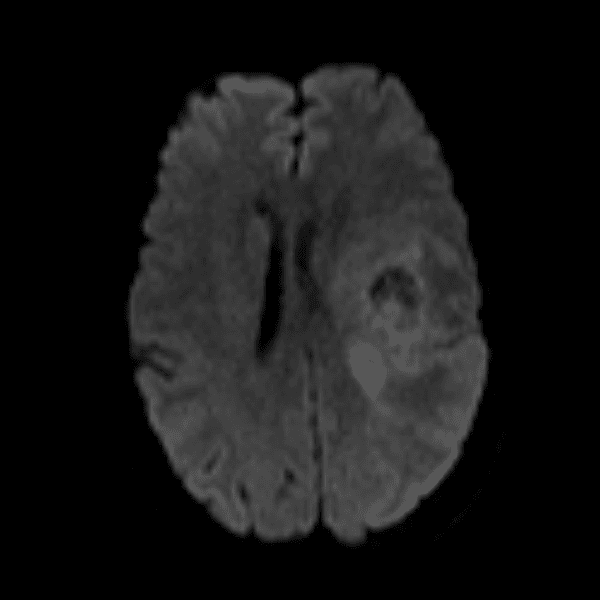

Classic Cases